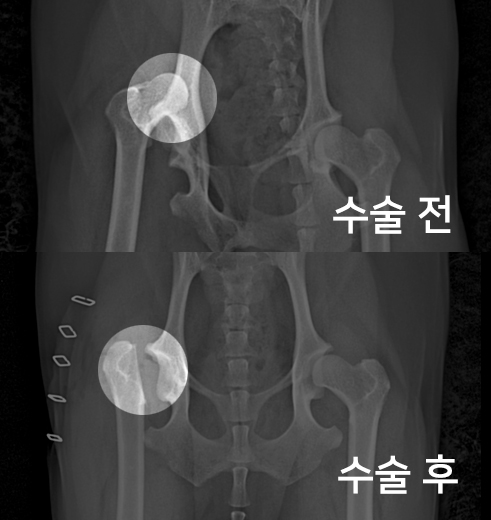

고관절 수술 사례 - #265 보리

보리는 오른쪽 다리가 계속 탈구되는 증상으로 내원하였습니다.

촉진 및 방사선 촬영 결과

대퇴골두 절골술(FHNO)이 필요하다고 판단되었습니다.

문제의 원인이 되는 대퇴골두를 깔끔하게 절단해 주었습니다.

수술 전과 수술 후 촬영한 고관절 방사선 사진입니다.

대퇴골두가 깔끔하게 절단된 것이 확인됩니다.

이제 재활 운동을 통해 체중을 지지할 근육을 키워주게 됩니다.